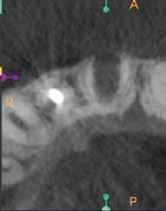

A kezelés befejezését követően 30 hónappal készített CBCT-felvételen a gyógyulás jelei észlelhetők.

Az elváltozást egy diagnosztikai céllal készített panoráma-röntgenfelvételen észlelték. Az elváltozás kiterjedésének pontos meghatározása, valamint a kezelési terv felállításának és a várható prognózis megítélésének elősegítése érdekében CBCT-felvétel készült (1. a–c ábra). A reszorbtív lézió a fog gyökerének középső harmadában helyezkedett el és a

1. a–c ábra: Kiindulási CBCT-felvétel. Az axiális síkú metszeten jól látható a gyökér falának perforációja (a); Koronális irányú metszet (b), Saggitális irányú metszet

8. a–e ábra: A kiindulási röntgen (a) és a kiindulási állapotról készített CBCT-felvétel (b–e). A felvételen jól látható a csatornafal és a bukkális kortikális perforációja.

Az IRR fennállásának gyanúja esetén mindenképp javasolt CBCT-felvétel készítése. A diagnosztizáláson kívül a kezelés pontos megtervezéséhez is rendkívül hasznosak a háromdimenziós felvételekből nyerhető adatok. Azt, hogy milyen stratégia mentén látjuk el a fogat, leginkább két fő tényező befolyásolja: A lézió alakja, és hogy van-e perforáció a gyökéren (1. táblázat). A fentiekben bemutatott esetek jól példázzák, hogy az egy ülésben végzett kombinált endodonciai és sebészi terápia alkalmas azon IRR-rel érintett fogak hosszú távú megtartására, ahol a gyökér már perforálódott és emellett a környező csontállomány is érintetté vált.